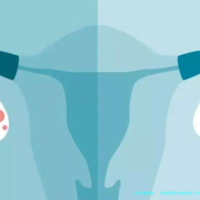

试管婴儿技术,在医学方面称为试管受孕-胚胎移植,是一种将卵子和精子取出体外,在实验室特殊环境中完成受精过程,再将构成的胚胎移植回母体子宫内发育的助孕方法。这一项技术主要适用于输卵管因素导致的不孕、男性精子质量问题、子宫内异症患者,以及缘由不明的不孕情况。

目前主流的试管婴儿技术分为三种:一代技术主要解决女性输卵管问题,让精卵在体外自在结合;2代技术针对男性精子问题,通过单精子注射方式强行做到受精;三代技术则是在胚胎移植前进行遗传生物学筛查,有效预防遗传性疾病传递,实现优生优育。